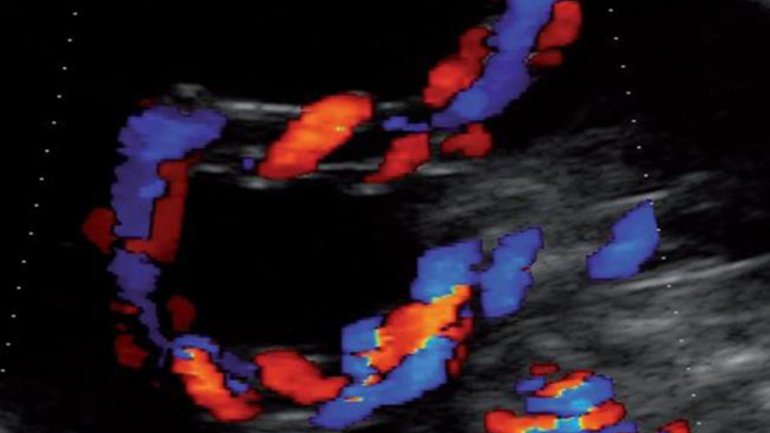

Ultraschall 16. SSW

Auf dem Ultraschallbild ist die Nabelschnur zu sehen; sie versorgt das Baby mit Nährstoffen und Sauerstoff und transportiert Abfallstoffe ab. Der Blutfluss in den drei Blutgefäßen (1 Vene, 2 Arterien) lässt sich mithilfe des sogenannten Dopplerultraschalls farbig darstellen und untersuchen.